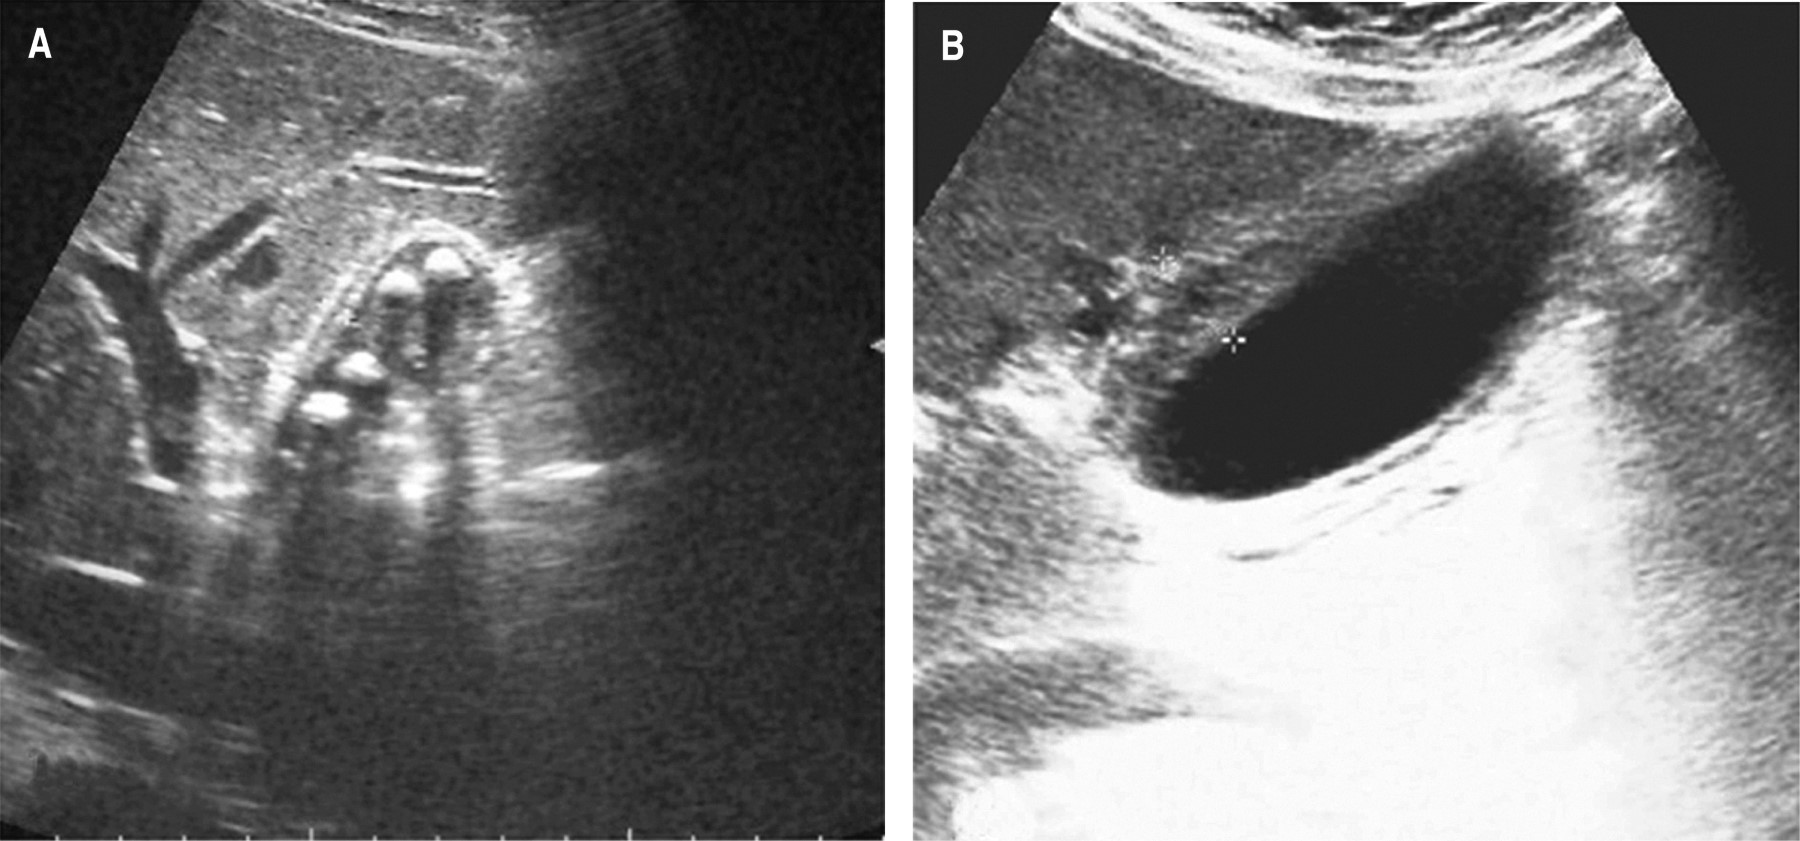

Figura 1